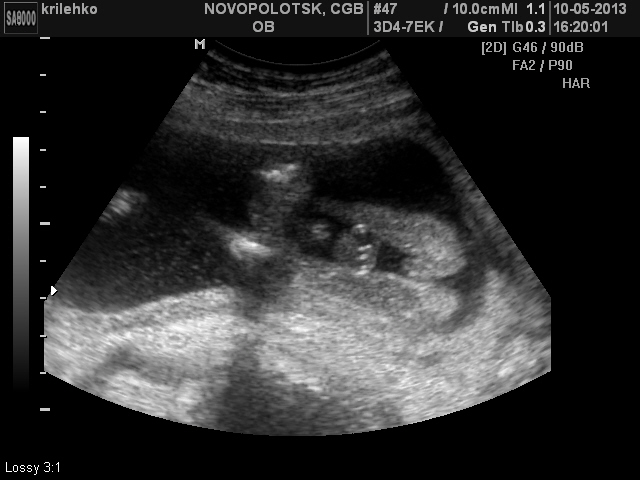

По-моему, абсолютно точно девочка. Где ж там девчонки писюн с яйками увидели? На первой фотке так вообще пирожок четкий)

Ну, если судить по 1-му снимку, то поцан точно))) А вы мальчика хотите?